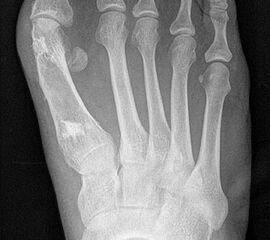

Die dorsoplantaren Röntgenaufnahmen zeigen eine Open-wedge Technik mit der normalerweise ein erhöhter intermetatarsaler Winkel gut zu korrigieren ist (Abbildung 3). Die Wirksamkeit einer Basisosteotomie ist umso größer, je proximaler diese durchgeführt wird. Je weiter distal die Osteotomie, umso geringer die Korrektur. Auf den postoperativen Bildern ist der distal unverändert große Abstand zwischen Metatarsale I und Metatarsale II erkennbar, bei gleichzeitiger Subluxation des Großzehengrundgelenks und dezentrierten Sesambeinen. Darüber hinaus finden sich initiale degenerative Veränderungen im Großzehengrundgelenk. Klinisch bestand eine hohe Weichteilspannung, bei verkürzter Extensor- und Flexor hallucis longus Sehne.  Daher wurde ein verkürzendes Verfahren zur Revision gewählt (Abbildung 4). Die Lapidusarthrodese stellt ein sehr zuverlässiges Verfahren zur Behandlung von Hallux valgus Rezidiven dar 9. Die Fusion des Tarsometatarsale-I-Gelenks kombiniert Stabilität mit einem hohen Korrekturpotenzial. Aufgrund der verfahrensimmanenten Verkürzung des ersten Strahls und der in diesem Fall bereits präoperativ vorhandenen Transfermetatarsalgie wurde die Entscheidung für eine verkürzte Weil-Osteotomie am zweiten bis fünften Strahl gefällt. Die Kombination beider Verfahren führte zu einem homogenen Metatarsale-Index und zu einer gleichmäßigen plantaren Druckverteilung 10. Die Hallux valgus interphalangeus Fehlstellung wurde mit einer Akin-Osteotomie korrigiert.